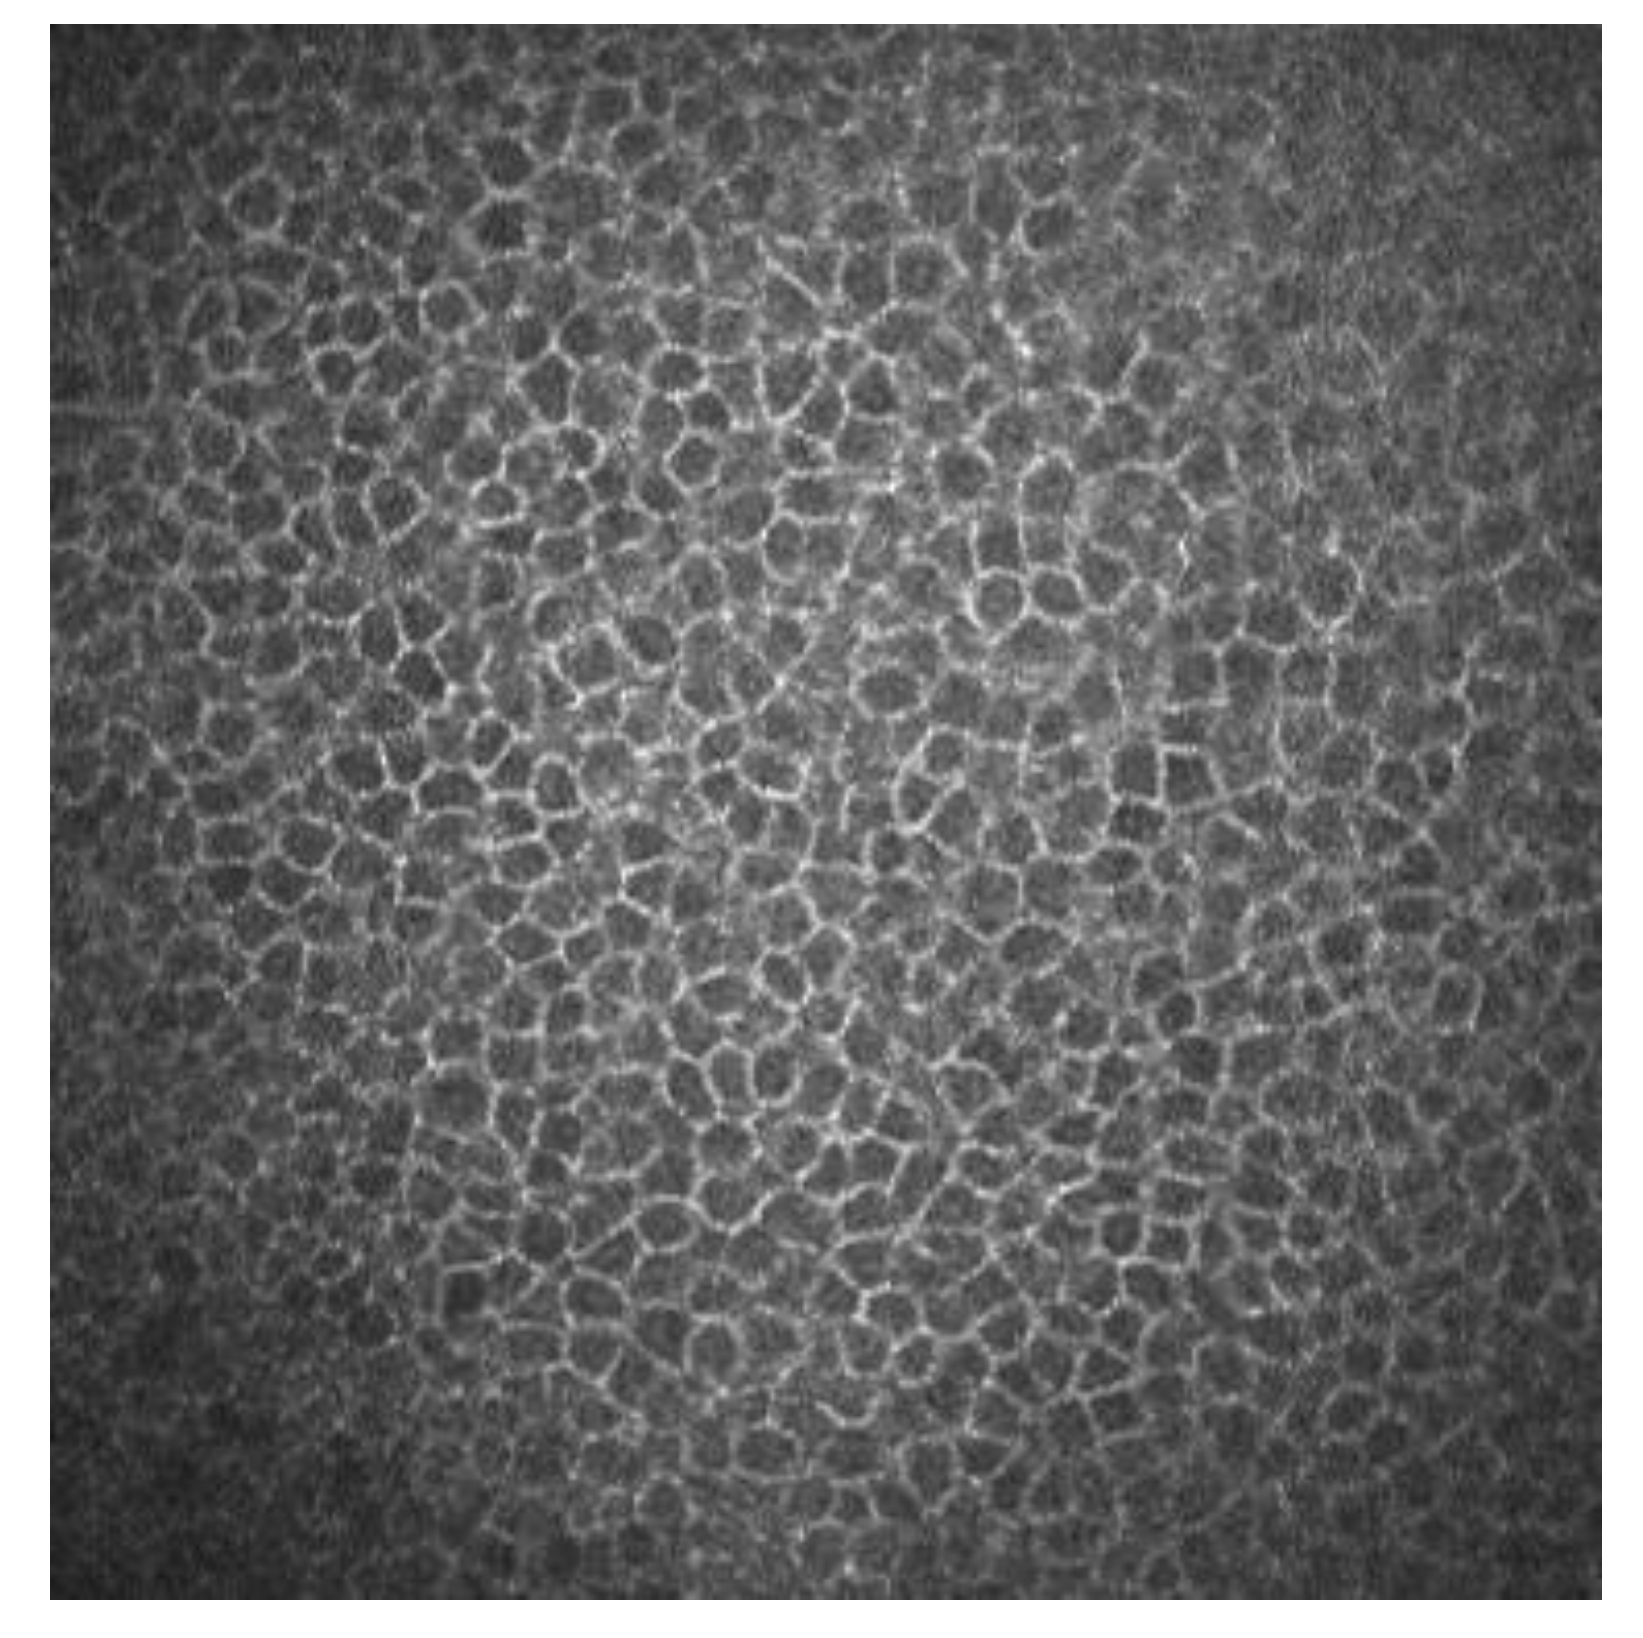

2.6. Endothelium

| Corneal Cells | Morphology | Reflectivity |

|---|---|---|

| Superficial epithelial cells | Polygonal, with different sizes | Hyperreflective nucleus surrounded by dark band |

| Winged epithelial cells | Polygonal, with different sizes | Hyperreflective without visible nucleus |

| Basal epithelial cells | Polygonal. Mosaic shape | Dark cell bodies with bright borders |

| Stromal cells (keratocytes) | Oval | Hyperreflective |

| Dendritic cells | Dendritic shape in active status. Oval shape in nonactive status | Hyperreflective |

| Nerve plexus | Lineal | Hyperreflective |

| Endothelial cells | Hexagonal shape | Bright cell bodies with dark borders |